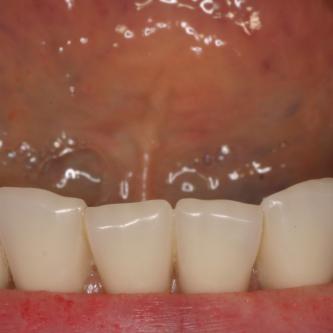

Exemple 1: Ce patient a perdu son incisive centrale gauche lors d'un accident. Un implant a été posé

Exemple 1: L'implant remplace la racine de la dent manquante

Exemple 1: L'implant s'est intégré dans l'os, une empreinte est effectuée. Le laboratoire peut réaliser la couronne en céramique.

Exemple 1: résultat final.